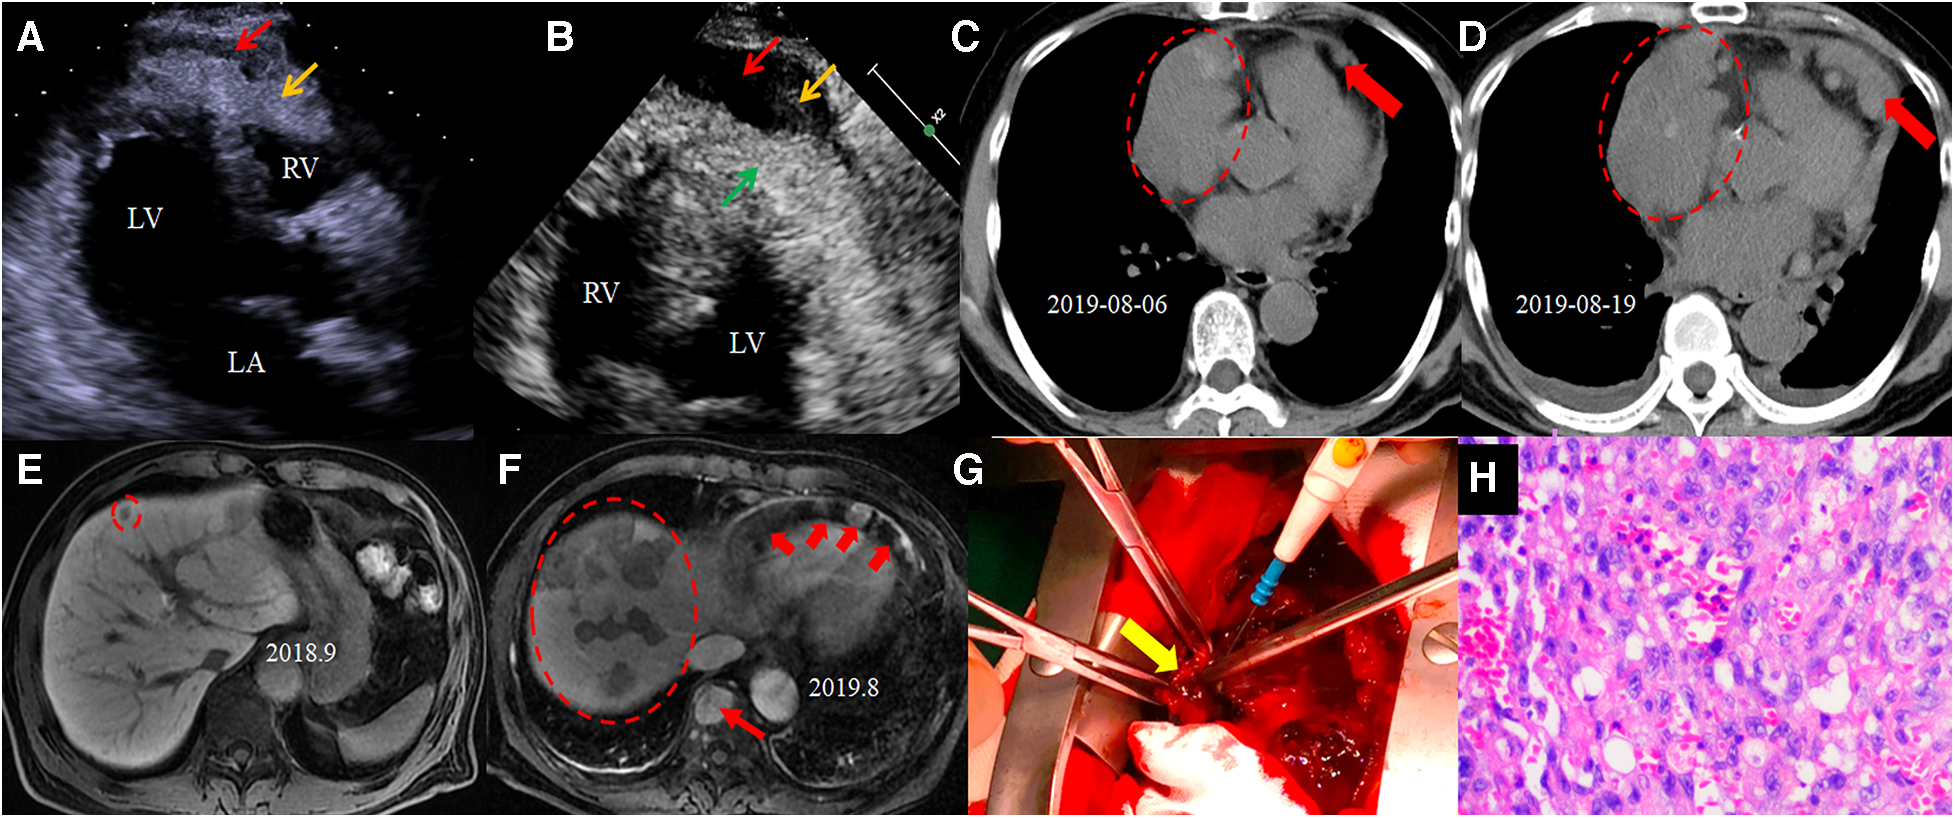

A 69-year-old male exhibited symptoms of fever, dry cough, and dyspnoea for a duration of 3 weeks. His past medical history included an uneventful surgery for a well-differentiated carcinoma of the colon (T1bN0M0, stage IA) 3 years ago, as well as hypertension and hyperlipidaemia. He quit cigarette smoking 20 years ago. No particular social history or family history of cancer was reported. A physical examination at admission revealed a body temperature of 37.6°C, a pulse rate of 109 beats per minute, a respiratory rate of 25 breaths per minute, and a blood pressure of 108/75 mmHg. The physical exam was otherwise unremarkable, except for tachycardia and muffled heart sounds. The laboratory findings showed leucocytosis (9.94 × 109/L) with neutrophilia (77.8%), an elevated C-reactive protein level (108.12 mg/L), and an elevated erythrocyte sedimentation rate (89 mm/h). The level of hypersensitivity cardiac troponin-T was mildly elevated at 0.04 ng/ml (reference range 0–0.024 ng/ml). The electrocardiogram showed sinus tachycardia. Transthoracic echocardiography demonstrated a normal left ventricular ejection fraction (63%) and bi-atrial enlargement. Heterogeneous echodensities in the apical pericardial space were noted (Figures 1A,B). Chest computed tomography (CT) after admission revealed newly developed pulmonary and hepatic lesions compared with the CT findings 1 year prior, when he had regular post-operation follow-up for colon cancer. The CT scan also revealed a heterogeneous mass located on the right side, lateral to the pericardium, which is larger than that observed 2 weeks prior on the outpatient CT scan (Figures 1C,D). Enhanced abdominal magnetic resonance imaging revealed multiple lesions in the liver and vertebral bodies (Figures 1E,F), which also included part of the heart and revealed ill-defined solid lesions involving the pericardial sac. The patient developed worsening dyspnoea, hypotension, and tachycardia and subsequently underwent a surgical pericardiectomy 25 days after admission. The pericardial space was found to be severely constricted by the haemorrhagic tumour tissues, but no pericardial effusion was present (Figure 1G). A palliative partial pericardiectomy was performed as the tumour had already infiltrated the myocardium and was unresectable. The diagnosis of pericardial angiosarcoma was confirmed through post-operative pathology of the pericardial tissue (Figure 1H), characterized by vimentin (+), AE1/AE3 (−), CD31 (+), CD34 (+), EMA (−), D2-40 (partially+), calretinin (−), and Ki-67 (25%+) on immunohistochemistry. Unfortunately, the patient died on the 12th day after the surgery due to cardiogenic shock and cardiac arrest. Table 1 lists the timeline and clinical course of the patient.

Figure 1

Iconography of the patient. The echocardiogram shows an echolucency (red arrow) and heterogeneous echodensities (yellow arrow) in the pericardial space in parasternal long axis view (A) and in apical four-chamber view (B) Chest CT (C) before admission reveals a heterogeneous mass (dotted ellipse) and pericardial nodules (red arrow). The repeat CT after admission (D) reveals an enlarged pericardial mass (dotted ellipse) and nodules (red arrow). The abdominal magnetic resonance hepatobiliary phase 1 year ago shows a low-signal nodule in the liver (dotted ellipse) on T2 weighted image. The magnetic resonance after this admission (F) shows multiple lesions involving the liver (dotted ellipse), spine (thin arrow), and pericardium (thick arrow). The gross specimen (G) shows a haemorrhagic solid tumour (yellow arrow) infiltrating the ventricular myocardium, and only partial pericardiectomy was performed. Histopathology (H) examinations confirmed the pericardial tissue to be angiosarcoma.